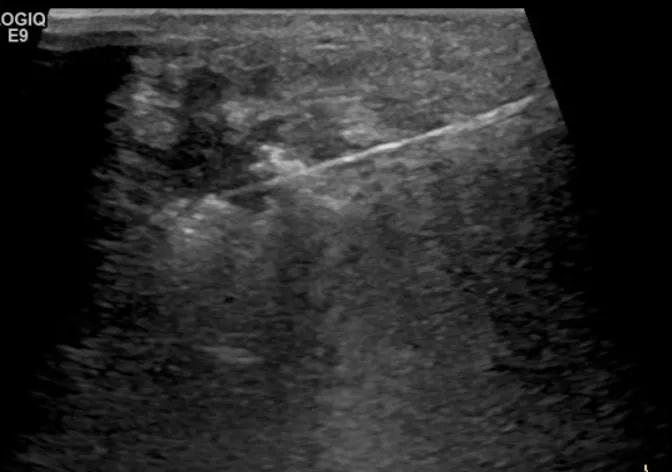

随后,徐栋教授进一步分享了五个临床实战病例,带来了更直观的热消融治疗经验。第一个病例是62岁肺癌患者,术后1年余发现双侧锁骨上淋巴结复发,侵犯神经,存在静脉回流、淋巴回流障碍,肿胀、疼痛非常明显。影像显示患者淋巴结边界不清、形态不规则,存在浸润,血流强化增强。由于患者在系统治疗后进展,且主要目的缓解症状、减瘤。局麻下行热消融术,从后向前逐层消融,热消融之后超声造影即刻评估显示完全充盈缺损,完全覆盖病灶。

(病例1图例)